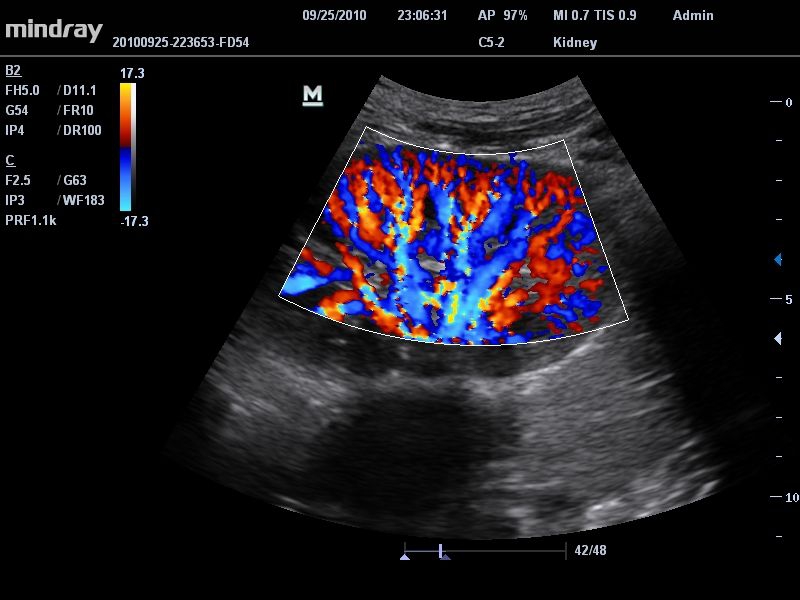

Цветовой допплер:

Да

Импульсно-волновой допплер:

• Режимы сканирования: B/M/CFM/PDI/Направленный PDI/PW, HPRF, Тканевая гармоника, М- и цветной М-режим.

Система сочетает в удобном и компактном корпусе не только традиционные возможности современного УЗИ-сканера, но и инновационные технологии, повышающие точности диагностики состояния пациентов.